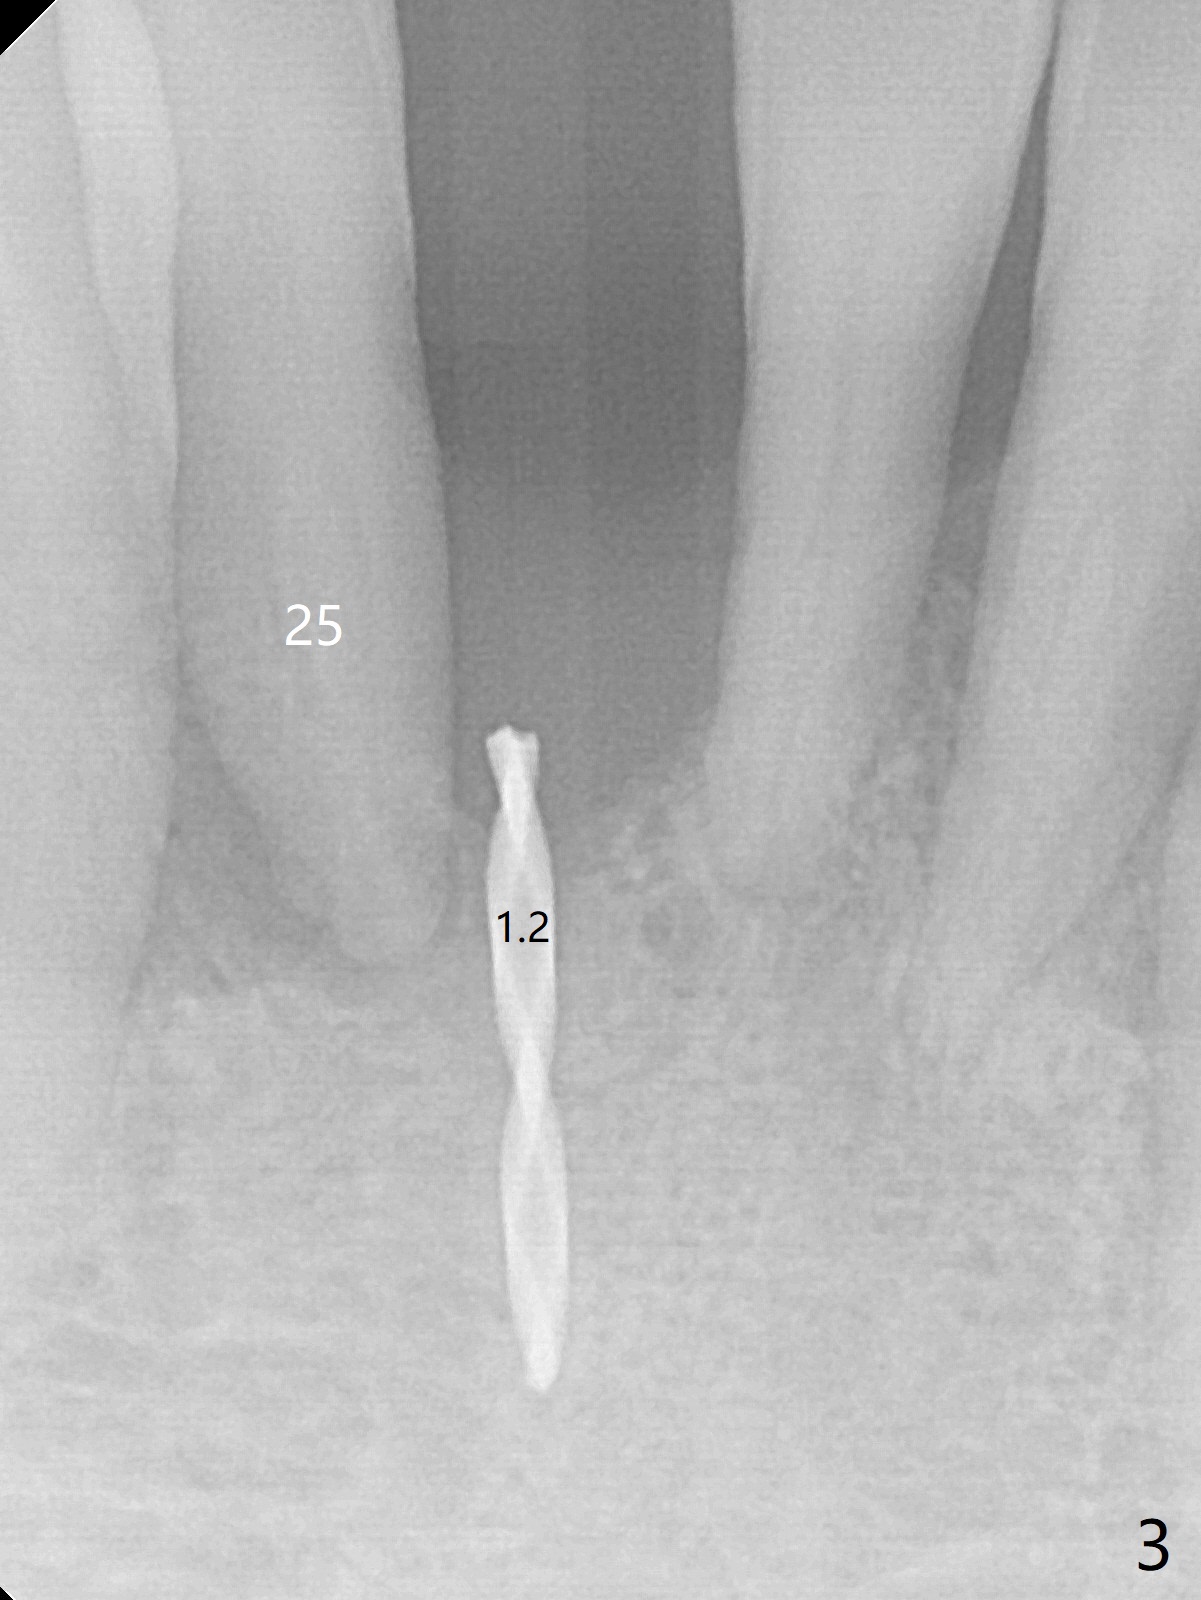

Out of financial concern, the patient does not agree to have the tooth #26 extracted. Due to atrophy of the most coronal ridge buccally at #25 (Fig.1,2 *), osteotomy is initiated difficult and distal (Fig.3). After 1.2 mm drill removal (Fig.3' black area), Lindamann bur is used to move the osteotomy mesial (red area). A 2x12(4) mm 1-piece implant is placed (Fig.4,5); the buccal defect is packed with allograft (Vanilla, .5-1 mm cancellous/cortical mixture, *). When the tooth #26 fails, a 2 mm implant will be placed (Fig.6 blue). Following abutment adjustment, a provisional is fabricated (Fig.7 P); note the lower incisal edges of #25 and 26, as compared to those of the neighboring teeth. To reduce occlusal trauma, the incisal edge of the tooth #26 has been decreased (Fig.5 open arrow). The implant threads seem not to be exposed 4 months postop (Fig.8), although the tooth #26 has mobility II.